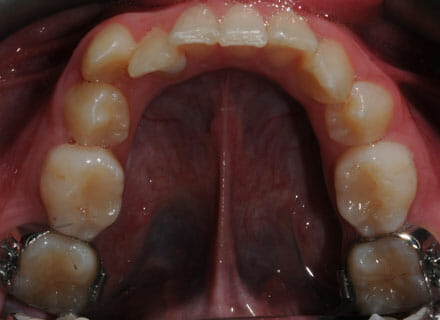

This lady hated her very uneven smile, all the teeth sticking out at the sides, teeth bunched together and uneven. We fitted clear brackets and a wire on the inside in the upper jaw in the roof of the mouth and in under 18 months the teeth were perfectly aligned and the patient’s smile was changed forever.